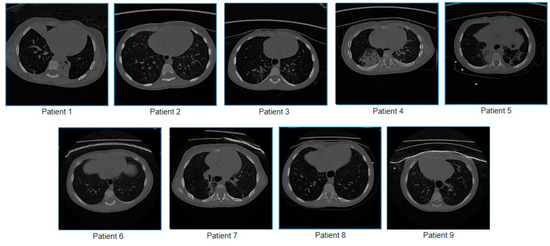

2.2. Participants

2.3. Sample Collection

| Data Acquisition Information | Technical Parameters Details | Patient Details | ||||

|---|---|---|---|---|---|---|

| Scanner: Philips Ingenuity Core 64 | Parameters | Parameter Value | No. | Sex | Age | Slice/Frames |

| Acquisition Mode | Spiral | 1 | Male | 5 years 6 months | 429 | |

| Single Collimation Width | 0.625 mm | 2 | Female | 3 years 3 months | 465 | |

| Scanner: Toshiba Aquilion | Total Collimation Width | 64 × 0.625 = 40 mm | 3 | Male | 2 years 8 months | 553 |

| Spiral Pitch Factor | 1.725 | 4 | Male | 1 year 10 months | 465 | |

| Kilovoltage Peak | 80 kVp | 5 | Female | 9 years 9 months | 689 | |

| Location: Royal Darwin Hospital, Northern Territory, Australia | Gantry Tilt | 0 | 6 | Male | 1 year 6 months | 54 |

| Reconstructed Slice Thickness | 0.67 mm | 7 | Male | 2 years 6 months | 20 | |

| DFOV (Average) | 170 mm | 8 | Female | 8 years 4 months | 26 | |

| Estimated Dose Saving (Average) | −10 | 9 | Male | 1 years 2 months | 24 | |